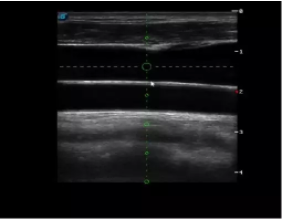

實時觀察穿刺針進(jìn)入血管的全過程,方便操作及較短的穿刺路徑,智能進(jìn)針尺寸提示,讓置管工作更加輕松,高效。

不同進(jìn)針路徑

TEE(經(jīng)食道超聲心動圖)將超聲探頭置入食道內(nèi),從心臟的后方向前近距離探查其結(jié)構(gòu) ,克服了經(jīng)胸超聲檢查的局限性,避免肺內(nèi)氣體、胸壁脂肪、胸廓畸形等因素影響,觀察角度更多,圖像更加清晰,測量數(shù)據(jù)更準(zhǔn)確。

經(jīng)食道超聲 大動脈短軸